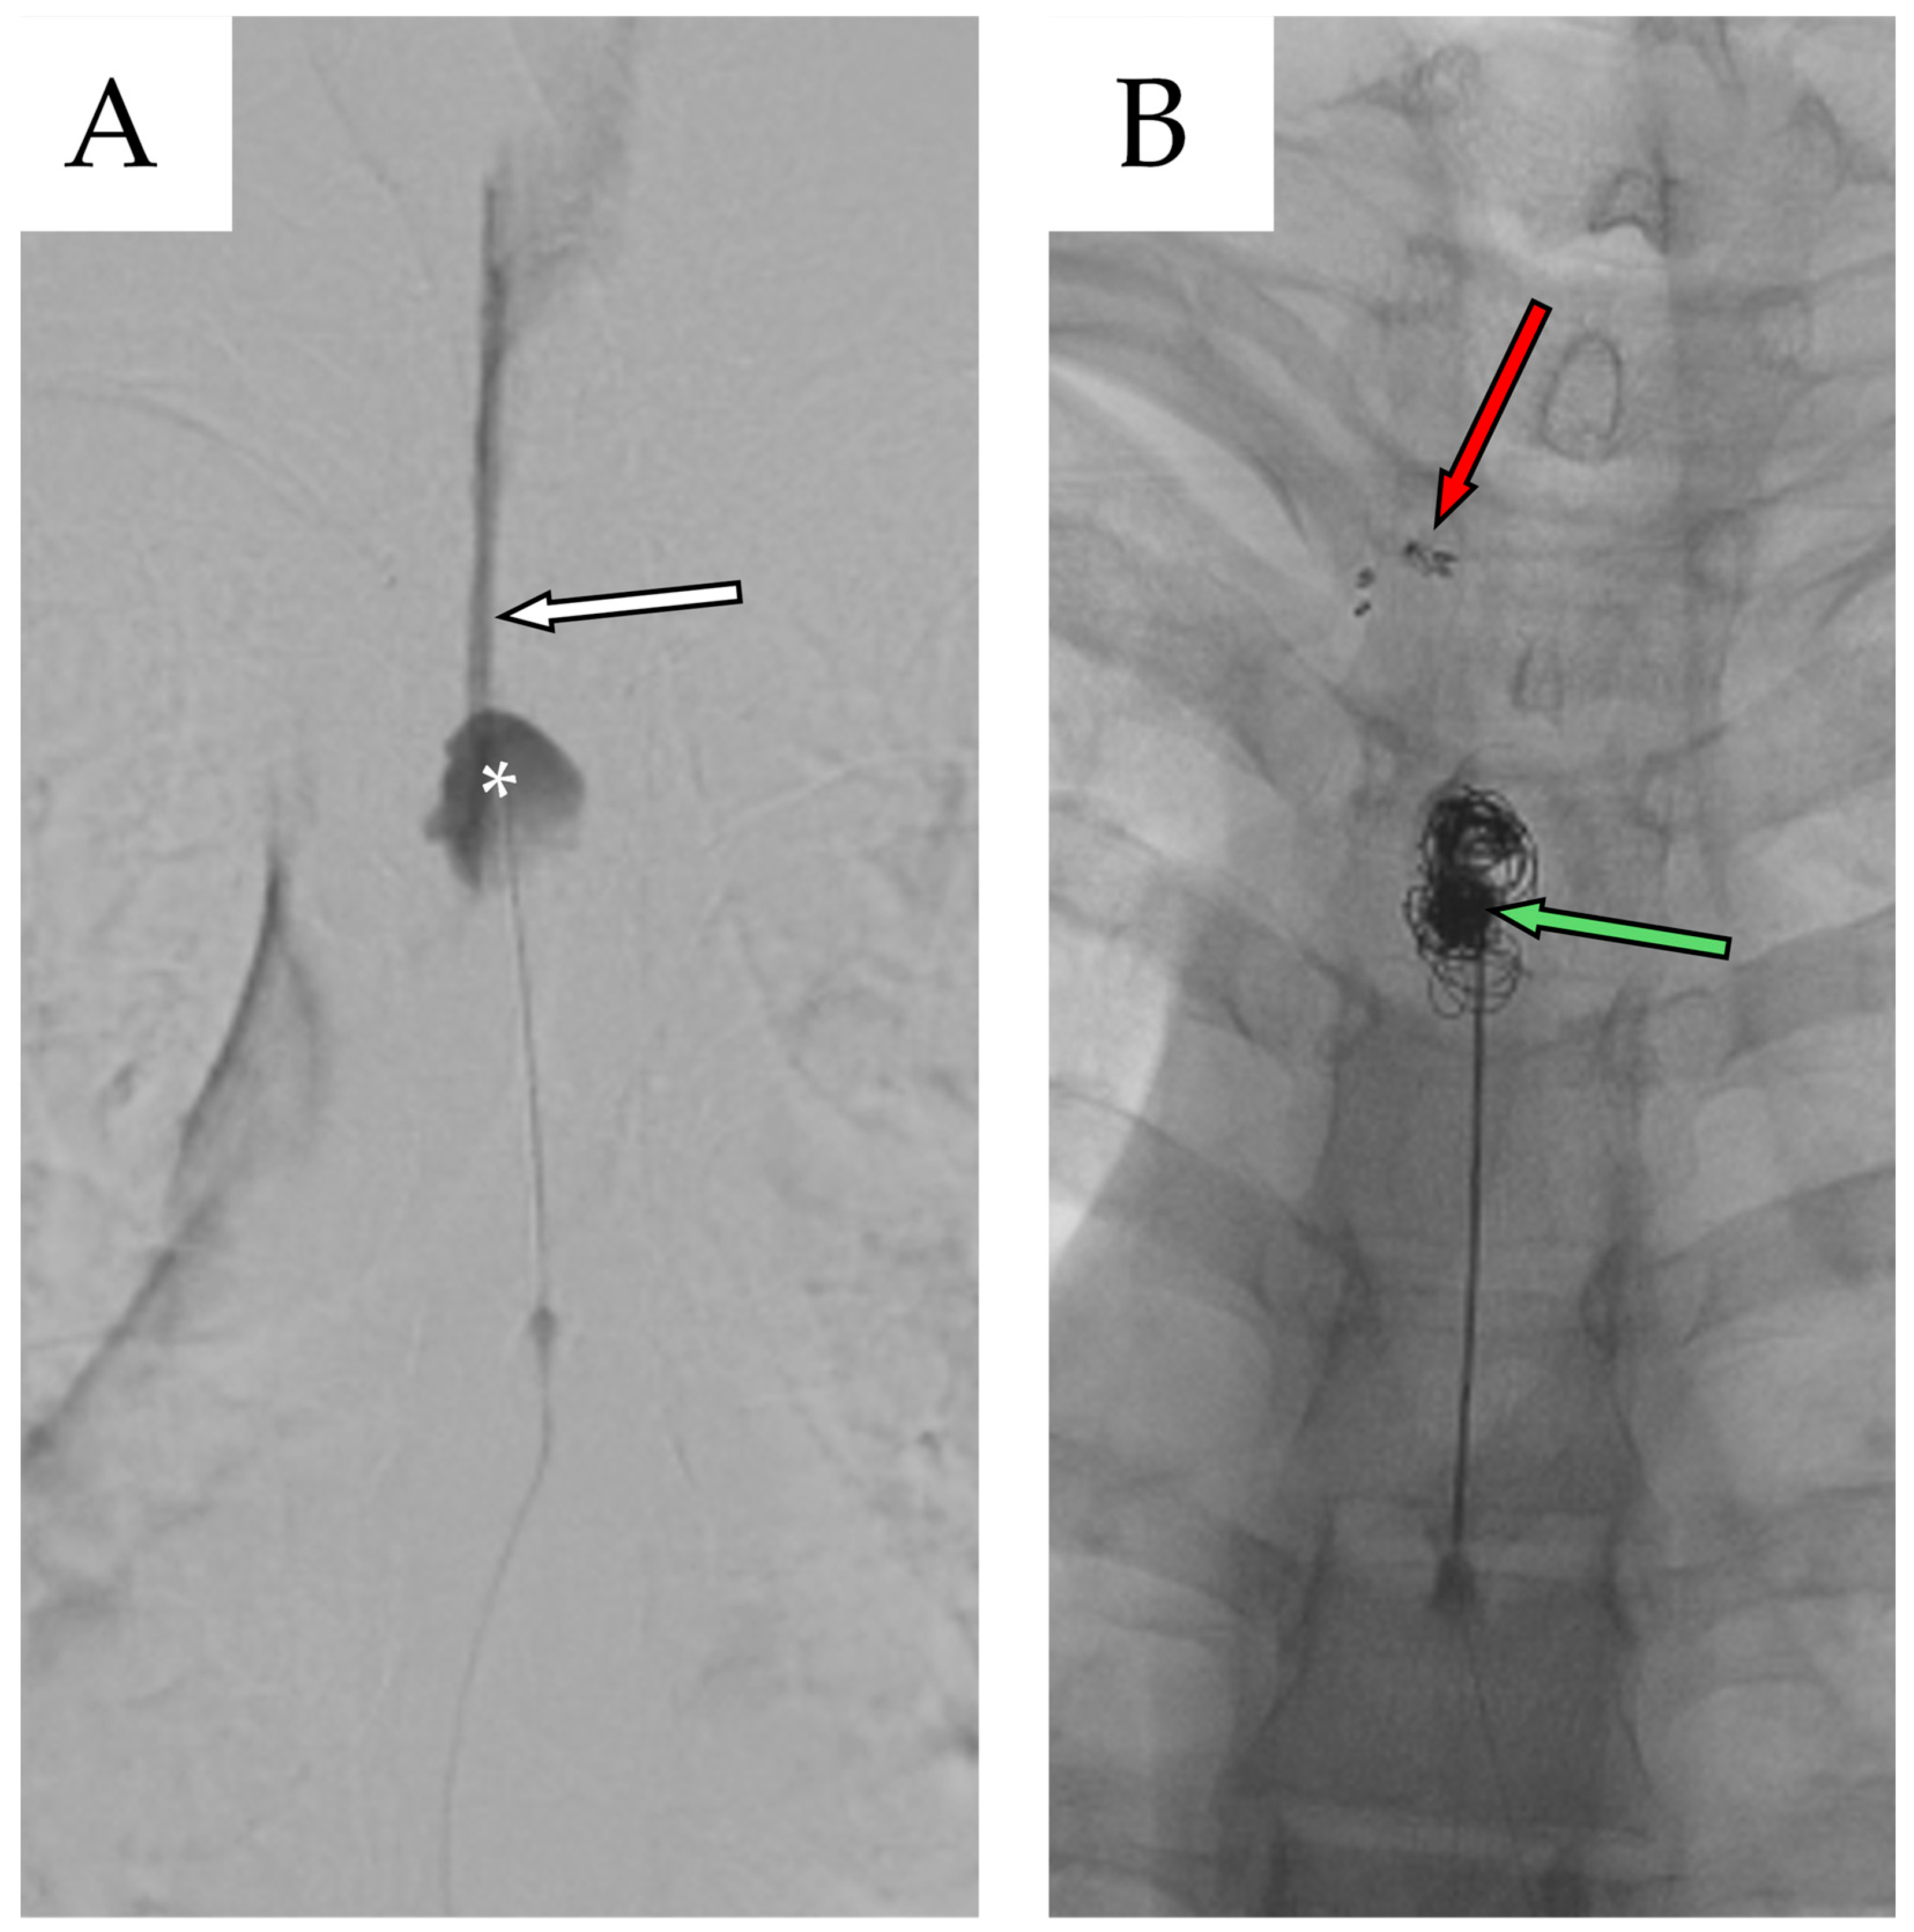

2.3. Second Admission

2.4. Second Follow-Up